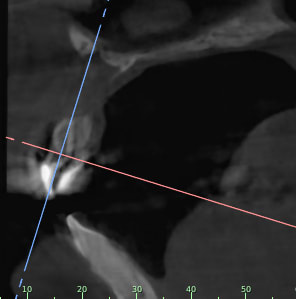

Je rajoutes quelques coupes et une rétro... C'est vraiment un massacre à la tronçonneuse!

24/04/2019 à 15h19

D'autres coupes et une rétro